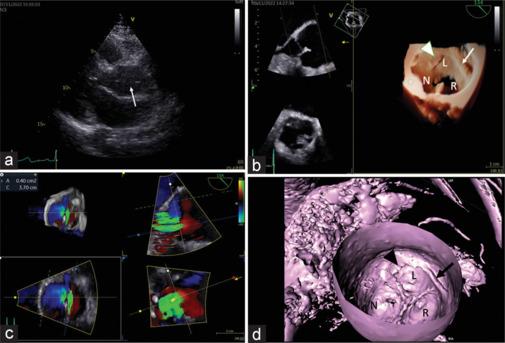

A 53-year-old woman was evaluated for left ventricular hypertrophy. Transthoracic echocardiography showed a mobile linear density in the ascending aorta and eccentric aortic insufficiency, raising the concern of aortic dissection. Transesophageal echocardiography and cardiac computed tomography (CT) found complex bands of tissue extending from the commissure to the aortic wall, confirming aortic valve tendon. It is an extremely rare malformation of aortic valve associated with aortic regurgitation that mimics aortic dissection. Although preoperative diagnosis has been challenging, three-dimensional echocardiography and CT reformatting aided the visualization of the spatially complex structure.

https://cdn.ncbi.nlm.nih.gov/pmc/blobs/3b48/12129266/1c4a352ff24e/JCE-35-74-g001.jpg